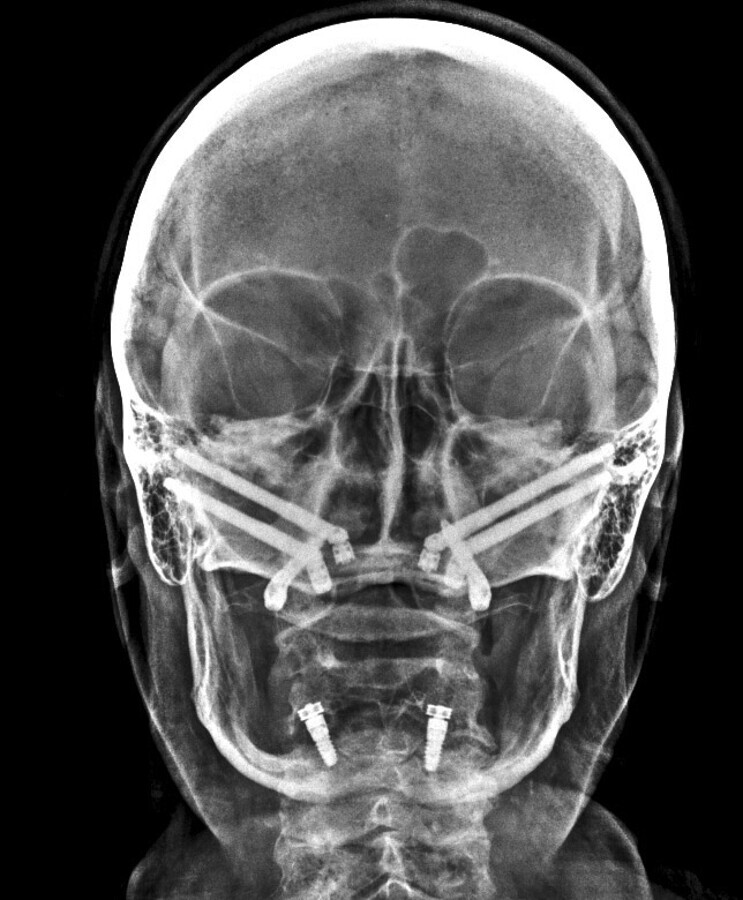

Implantología con anclaje extramaxilar

Mario Venturini, director del Instituto de Cirugía Maxilofacial en Rosario, Argentina, nos cuenta el tema que impartirá en la Jornada Virtual de Implantología de AIOI, que versará sobre “Implantología con anclaje extramaxilar”, técnica que permite reconstituir el arco dentario completo del paciente.

La implantología impulsó una mejora en la calidad de vida de los pacientes, mejorando notablemente no solo su confort y estética sino también su autoestima. Aunque pareciera poco y no lo es, evitó dañar más piezas dentarias para lograr un mismo resultado. Si todo ello es cierto, válido y genuino, el anclaje extramaxilar vino más aún, hace ya tiempo, a dar otro gran salto en la resolución quirúrgico protésica en un sesgo de pacientes que seguían excluidos de los beneficios de la implantología por razones obvias: carecían de stock óseo donde implantar.

La implantología volvió a los pacientes más ambiciosos y demandantes de importantes rehabilitaciones, y con justa razón. Hoy en día, prácticamente no hay límites ni etarios ni resortivos-resectivos en los cuales no pueda lograrse la mayor de las rehabilitaciones, el mayor gold estándar, al que los pacientes pueden aspirar: me refiero, ni más ni menos, que a reconstituir su arco dentario completo fijo. Incluso con la posibilidad de remoción y mantenimiento que un simple mortal no implantado no tiene.